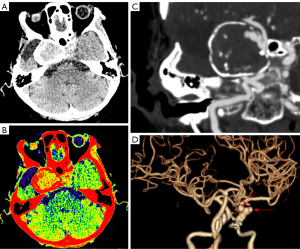

MRI revealed a mass with a short T1 and T2 signal in the right cavernous sinus region, measuring 3.2 cm × 3.9 cm × 3.1 cm. The lesion included flocculent areas with slightly high signal intensity on T2-weighted imaging with an onion-skin appearance (Figure 2A,2B). Nodular enhancement was observed in the lesions (Figure 2C). The nodular enhancement lesions displayed hyperperfusion on the arterial spin labeling sequence (Figure 2D).

The three-dimensional TOF-MRA revealed a GIA on the C4 segment of the right ICA (Figure 2E). Finally, digital subtraction angiography (DSA) was performed to accurately evaluate the patient’s condition. The results revealed three aneurysms in the C4 segment of the right ICA (Figure 2F,2G). The largest aneurysm measured approximately 35 mm × 32 mm, and its neck was 16 mm. Thrombosis was observed in the aneurysm. The aneurysm was successfully embolized with stent-assisted embolization, and the stent completely covered the neck of the aneurysm and adhered well to effectively block the blood flow within the aneurysm and reduce the risk of internal leakage (Figure 2G).